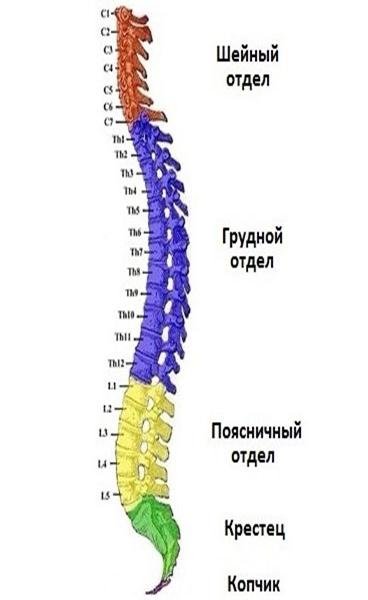

Отделы позвоночника для мрт схема фото и названия